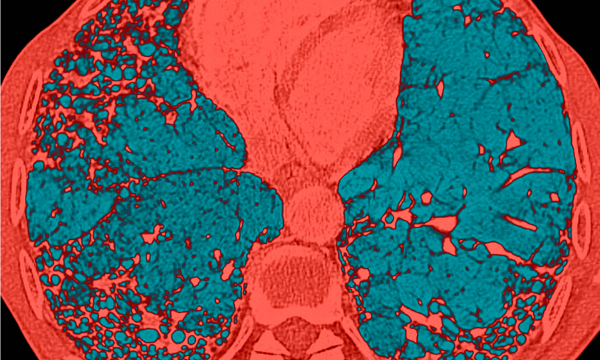

Idiopathic pulmonary fibrosis is a life-limiting interstitial lung disease. We do not know what causes it and there is no cure. People experience debilitating symptoms and delays before a diagnosis is confirmed are not uncommon. Palliative and end of life care for these patients is of variable quality. This article introduces and discusses the complexities of recognition, treatment and management of idiopathic pulmonary fibrosis, emphasising the importance of the primary care and community nurse roles. The implications for nursing practice in managing this group of people to live well and to die well will be explored.